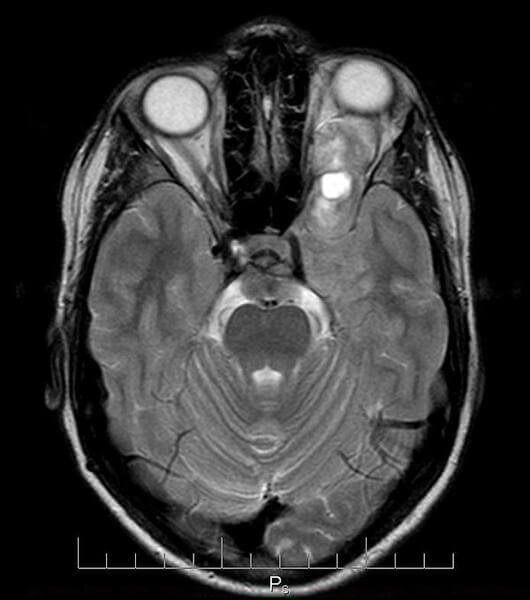

МРТ ГЛАЗНЫХ ОРБИТ ПРИ ЗАБОЛЕВАНИЯХ СЛЕЗНОЙ ЖЕЛЕЗЫ

В медицинских центрах СПб исследование МРТ слезной железы делают как часть магнитно-резонансного обследования глаза. Как самостоятельное обследование МРТ слезных желез не существует. Для информативной диагностики заболеваний этого органа необходимо сделать магнитно-резонансное исследование на высокопольном томографе мощностью не менее 1,5 Тесла. Направление на МРТ глазных орбит, как правило, дает врач окулист. МРТ - это метод диагностики, который использует магнитное поле и радиоволны для получения изображения, восстановленного математическими методами. За несколько десятков лет существования МРТ данный метод медицинской визуализации претерпел бурное развитие и на сегодня является доминирующим видом диагностики для большинства заболеваний.

Современное оборудование в десятки раз быстрее осуществляет сканирование и обработку данных. Это происходит со значительным улучшением качества визуализации. Особенно ценят офтальмологии МРТ за ее высокую разрешающую способность и межтканевой контраст. С помощью магнитно-резонансной томографии глазных орбит и пазух носа врач получает все необходимые данные, сопоставимые по точности с анатомическими срезами в любых плоскостях. Для пациента этот метод привлекателен тем, что он неинвазивен. Для обследования глаз и мышечных структур вокруг них не используются никакие препараты, которые нужно закапывать в глаза, или иное механическое вмешательство. Также полностью отсутствует лучевая нагрузка на пациента. МРТ глазных орбит показывает:

• состояние тканей глазного яблока, зрительного нерва;

• аномалии в размерах и положении слезной железы;

• повреждение мышечной ткани;

• дистрофию жировой прокладки;

• расширение, сужение, мальформации глазных артерий и вен.